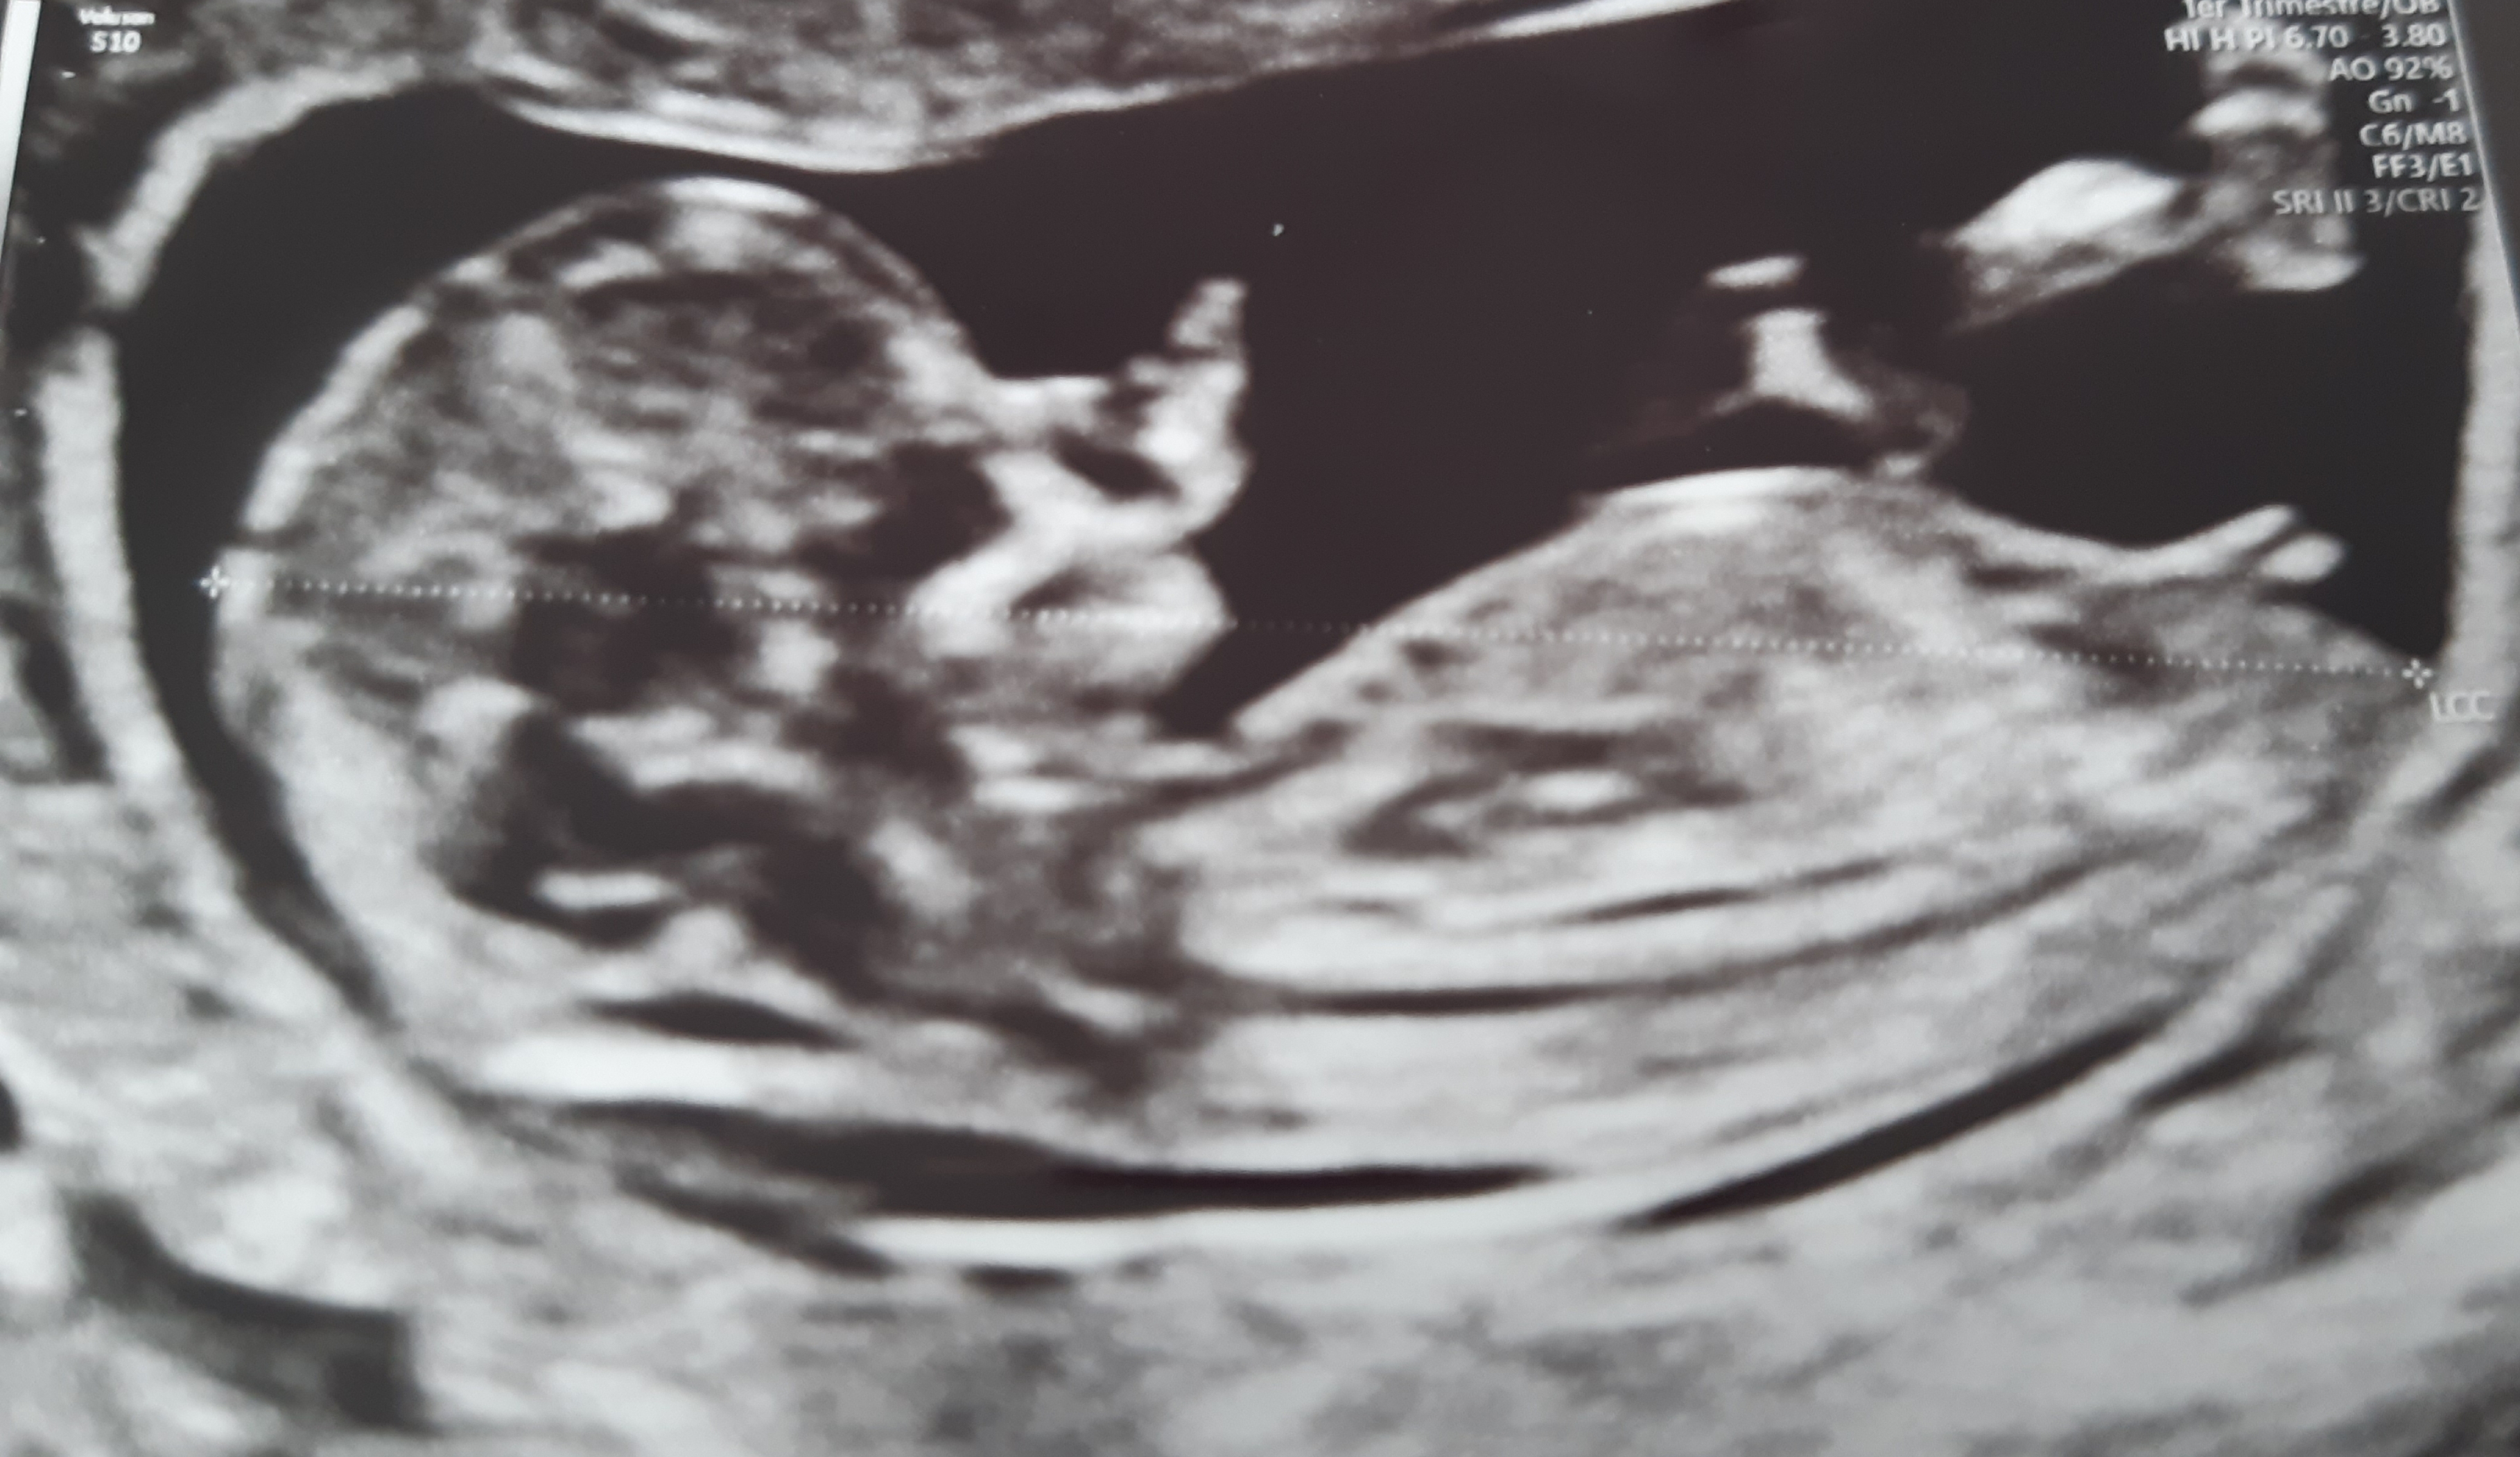

QUE REGARDE-T-ON EXACTEMENT ?

L'examen au cours de la grossesse comporte quatre parties dont l'importance relative varie selon le terme:

- Appréciation de la vitalité (activité cardiaque, mouvements, ...).

- Etude biométrique par la mesure de certaines parties déterminées afin de préciser le début de grossesse (si l'examen est précoce) et de surveiller la croissance.

- Analyse morphologique par l'observation de certaines structures foetales (organes ou parties d'organe) définies, connues pour leur utilité dans le dépistage de pathologies fréquentes et/ou sévères.

- Observation de l'environnement du foetus (liquide amniotique, placenta, Doppler ...).

La réunion de tous ces éléments constitue un bilan de santé de votre enfant, inaccessible par toute autre méthode, qui renseigne sur son état immédiat mais aussi sur certains risques de pathologie pouvant se manifester plus tard au cours de la grossesse ou même après la naissance.